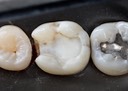

Larry Fujioka #4-5 pre-op